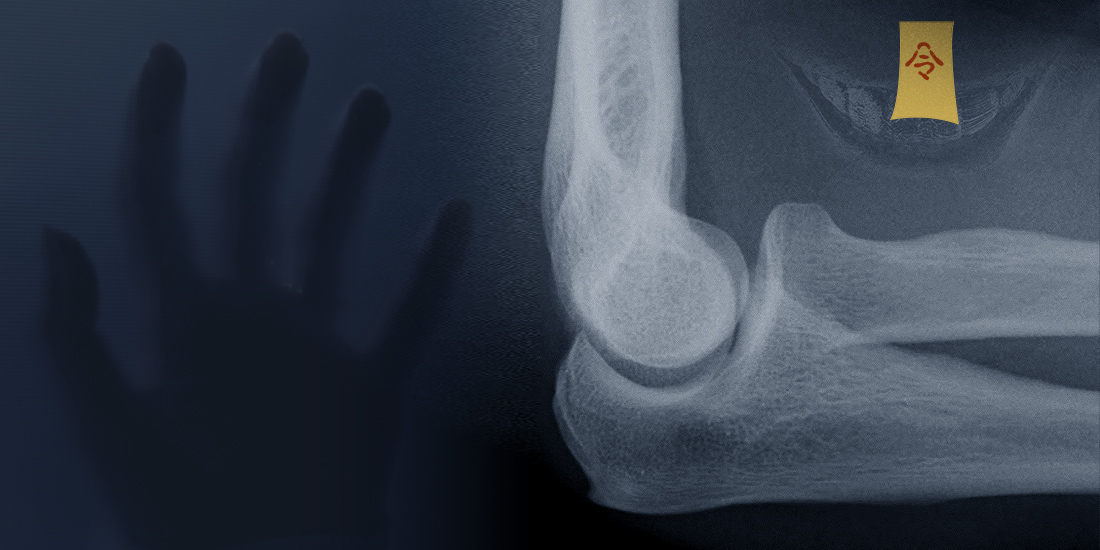

舉例來說,一張手肘的X光,我們可以藉由對比的差距看出空氣、皮下組織、肌肉跟骨骼的灰階差異。如果在同一階層中,出現密度不同的影像。那就有需要注意是否有異常。皮下如果出現多個小黑點,有可能是表皮有受傷空氣跑入皮下組織。肌肉層下出現大片的陰影,可能是血腫。骨骼內出現線性的黑色線條,可能是骨折。

但,血管可能走在骨骼之中,關節或神經附近會有脂肪或是滑膜保護,這時候在影像上在同一階層中會呈現陰影。或是重疊的骨頭可能在影像上會顯現的更白,像是遠端肱骨的直徑增加呈現三角錐的結構,側面照時骨骼就會因為穿透的骨質較多而呈現較白的色階。